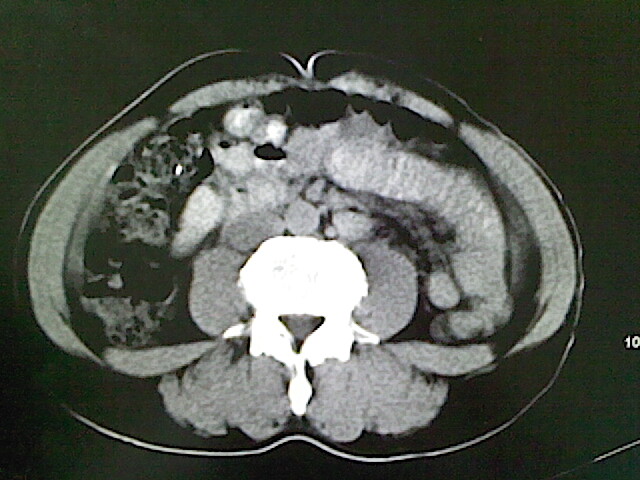

标题: CT18630:男,54岁,乙肝,大家看怎么样? [打印本页]

男,54岁,乙肝,大家看怎么样?

肝脏的要有增强敢说话

未见明确异常;建议必要时行ct增强扫描检查。